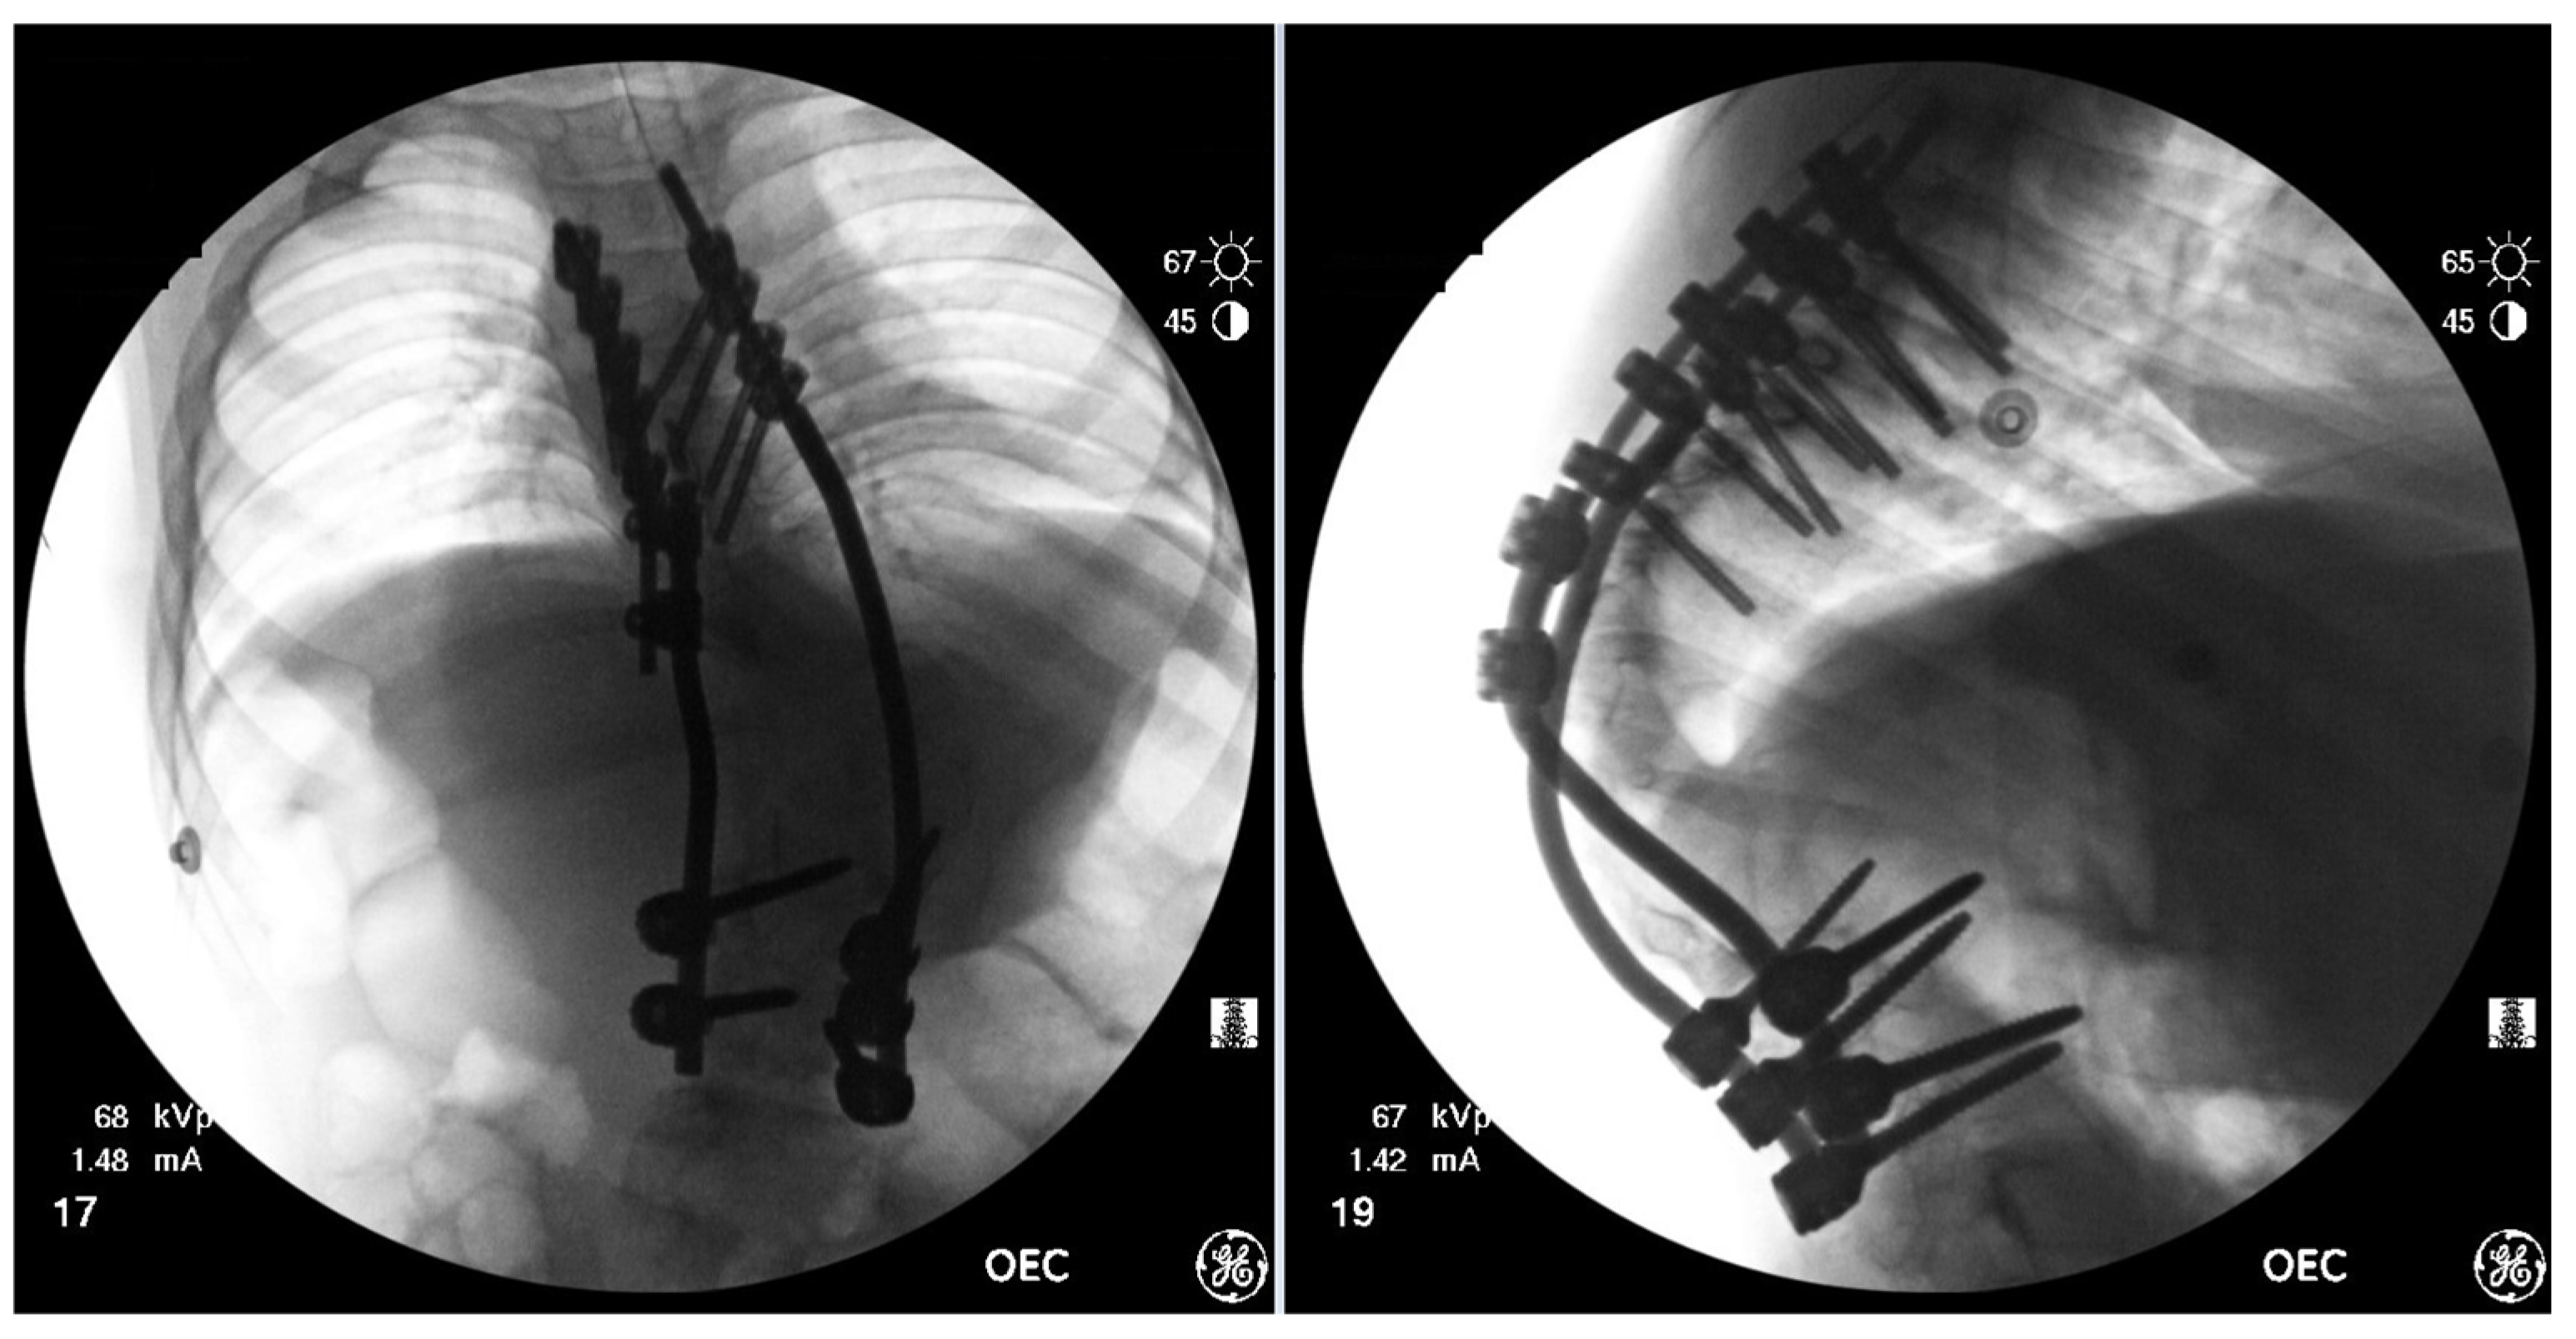

Figure 7.

AP & Lateral fluoroscopy images of temporary spinal instrumentation stabilization.